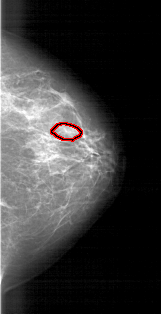

A_1770_1.LEFT_MLO

FILE: A_1770_1.RIGHT_MLO.OVERLAY

TOTAL_ABNORMALITIES 1

ABNORMALITY 1

LESION_TYPE MASS SHAPE OVAL MARGINS OBSCURED

ASSESSMENT 3

SUBTLETY 3

PATHOLOGY BENIGN

TOTAL_OUTLINES 1

BOUNDARY